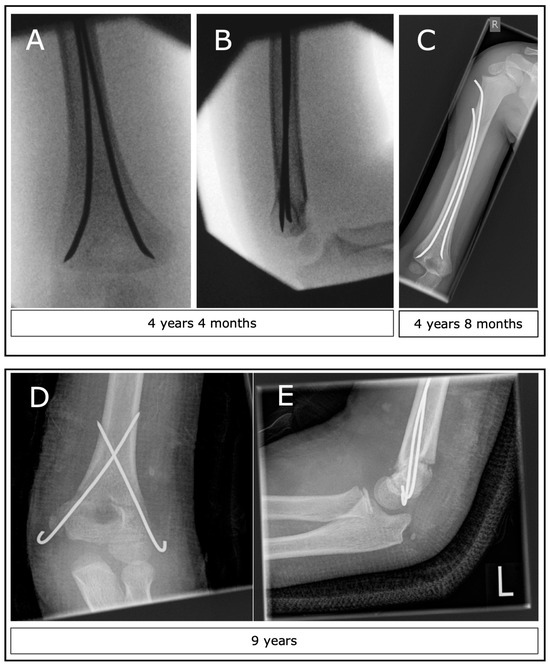

3.6. Operative Technique (CRK, ESIN, ORK)